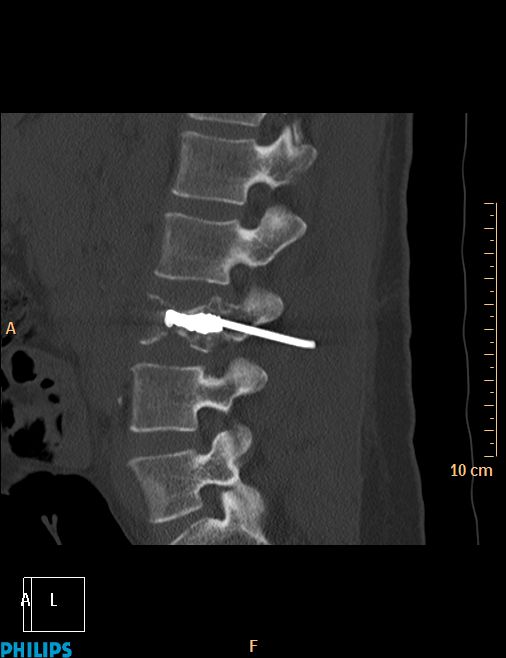

La vertébroplastie C'est ça d'attendre trop avant de retirer le trocard !!!